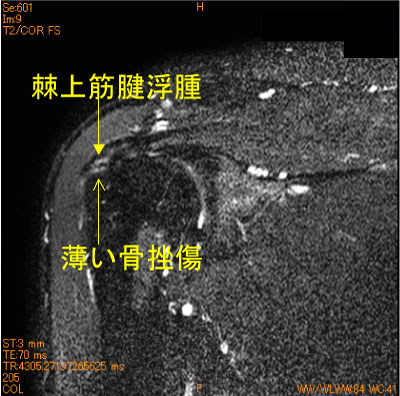

上腕骨大結節不全剥離、棘上筋腱停止部損傷

40代男性。テニスのサーブ時の痛み。水泳歴30年。

棘上筋腱停止部は僅かに脂肪抑制T2 high signalを認めている。